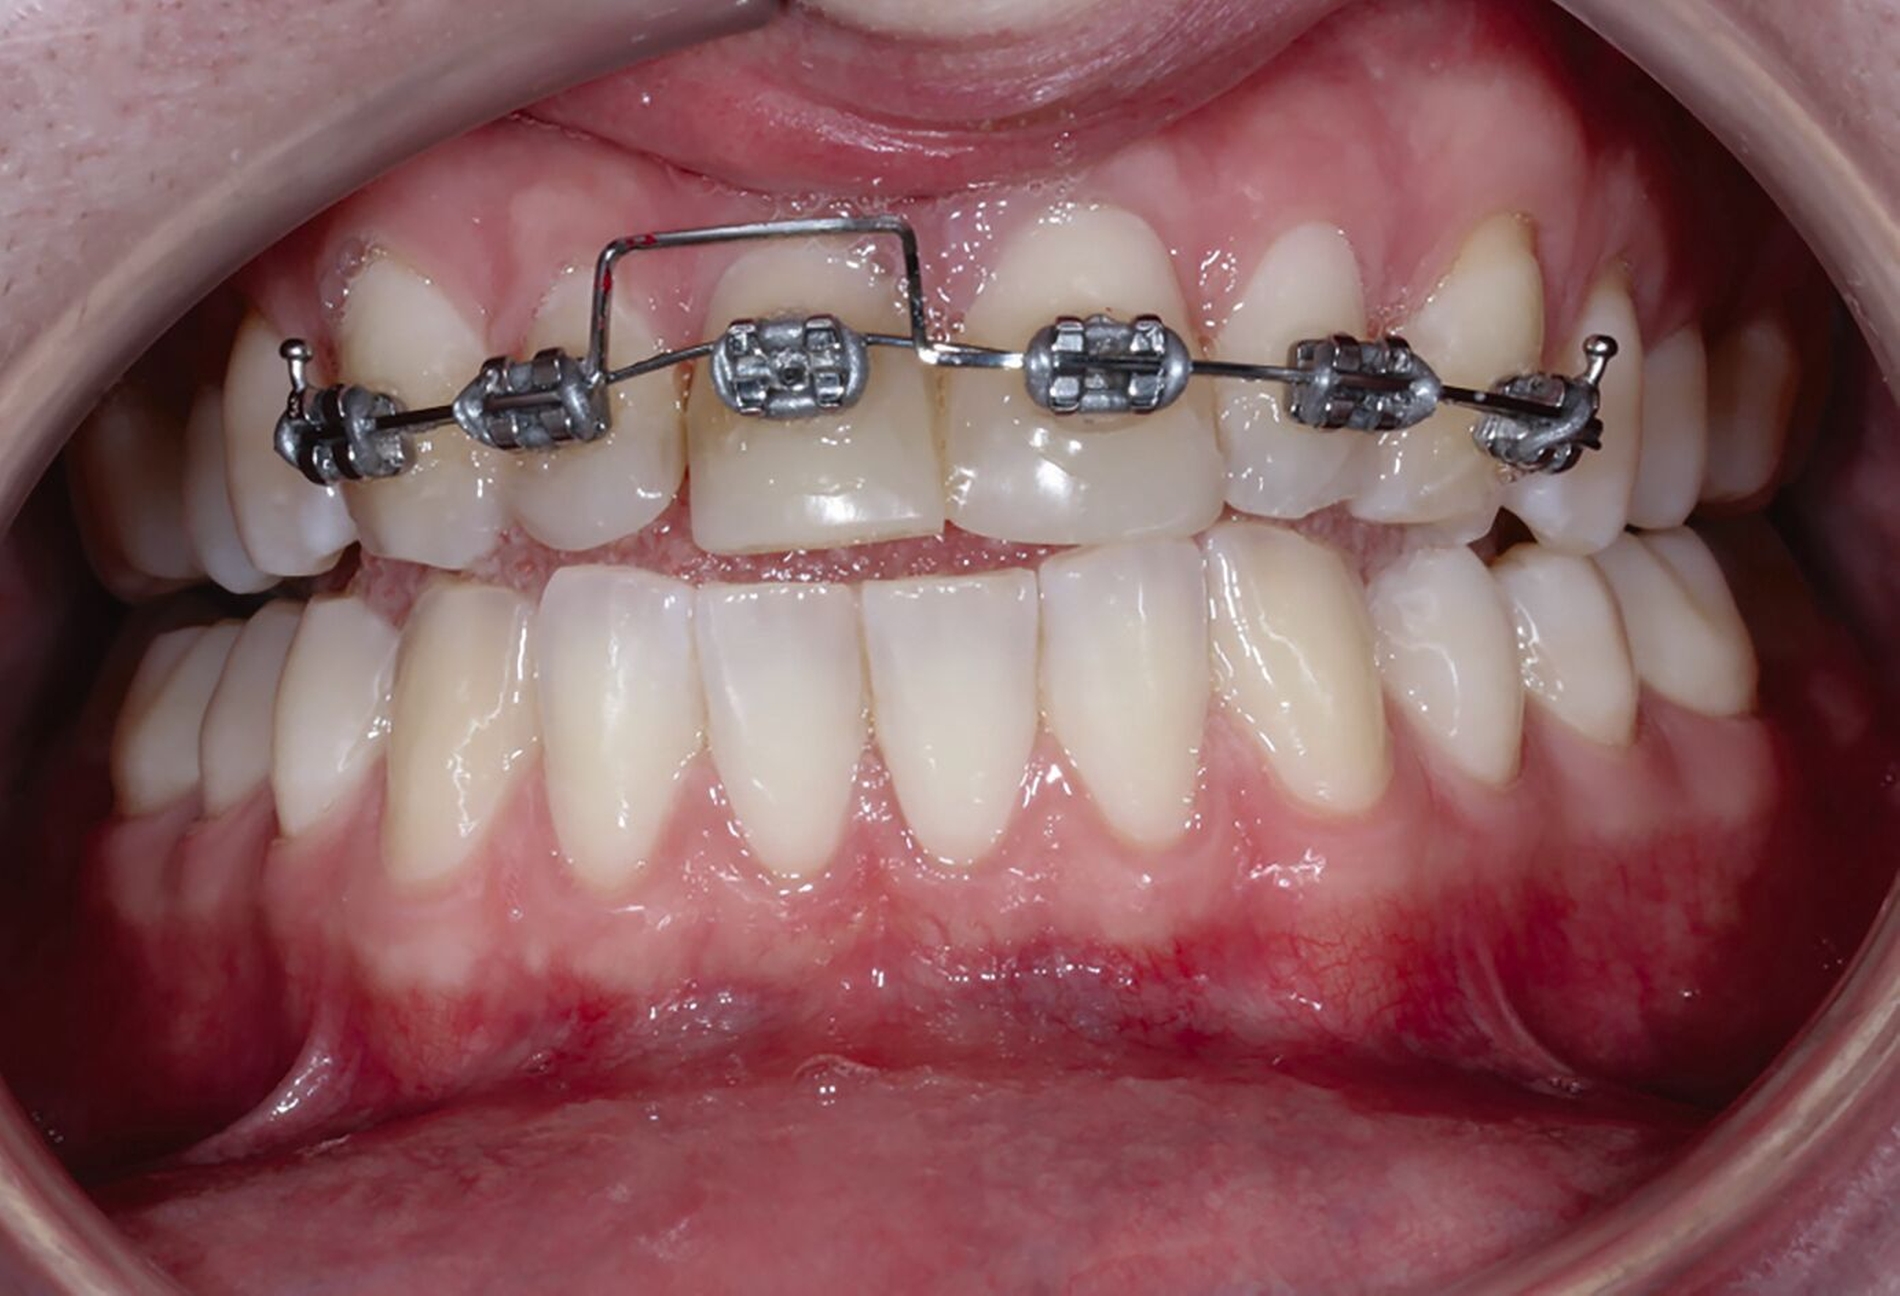

Nachfolgend konnte die Multibracket-Apparatur (MBA) für die Extrusion in Segmentbogentechnik befestigt werden (Abbildung 10). Dazu wurden die zu beklebenden Kompositflächen mit Aluminiumoxid-Pulver gestrahlt und mit einem Silan-haltigen Haftvermittler benetzt. Anschließend wurde drei Monate die kieferorthopädische Extrusionstherapie durchgeführt (Abbildungen 10 bis 12). Der Patient stellte sich wöchentlich zur Fibrotomie vor, um eine Verlagerung der Gingiva nach koronal zu vermeiden. Aufgrund der nach koronal gerichteten Bewegung erfolgte im Bedarfsfall das Einkürzen der Schneidekante.

Die Zähne 11 und 21 wurden nach Abschluss der kieferorthopädischen Behandlung mit Lithiumdisilikat-Keramikkronen versorgt (Abbildungen 14 bis 16). Durch die Extrusion waren das Fassen der Frakturkante und die Etablierung des Ferrule-Effekts nun ohne Probleme möglich. Die Eingliederung der Arbeit konnte unter absoluter Trockenlegung erfolgen. Die nach dem Einsetzen angefertigte Einzelzahnaufnahme zeigt die präzise Adaptation der Kronen sowie Umbauprozesse des Alveolarkamms. Drei Jahre nach Therapieabschluss zeigt sich eine suffiziente klinische Situation (Abbildung 17).